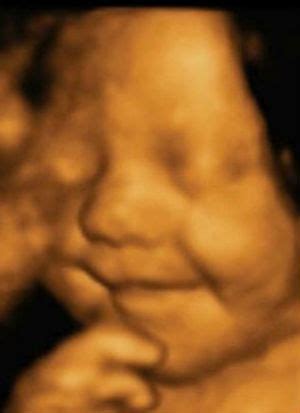

4D echoskopija yra moderni ultragarso technologija, leidžianti matyti trimačius vaizdus su judesiais realiu laiku. Kitaip tariant, 4D echoskopija yra patobulinta 3D echoskopijos versija, kuri pridėta ketvirtoji dimensija - laikas. Tai reiškia, kad galite matyti savo kūdikį ne tik kaip statinį vaizdą, bet ir stebėti jo judesius: šypseną, rankyčių judesius ar net čiulpti nykštį.

4D echoskopija dažniausiai atliekama tarp 26 ir 32 nėštumo savaitės. Šiuo laikotarpiu kūdikis jau yra pakankamai išsivystęs, kad būtų galima aiškiai matyti jo veido bruožus ir judesius. Ankstyvuoju nėštumo laikotarpiu kūdikis yra dar per mažas, kad būtų galima gauti aiškius vaizdus, o vėlesnėse savaitėse vaisiaus dydis ir amniono skysčio kiekis gali apsunkinti geros kokybės vaizdų gavimą.

- Emociniu požiūriu - 4D echoskopija suteikia unikalią galimybę tėvams pirmą kartą susitikti su savo kūdikiu. Šis emocinis ryšys, kurį tėvai užmezga matydami savo vaiką, gali būti neįkainojamas. Daugeliui šeimų tai yra nepamirštamas ir jaudinantis momentas, kuris sustiprina jų ryšį su būsimu vaiku.